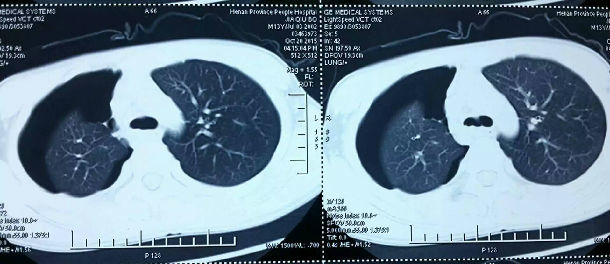

又是气管隆突下成形术。13岁男孩10月11日骑摩托车外伤,当时某大医院支气管镜发现右主支气管断裂,呼吸尚可,一直观察处理。待呼吸困难出现,又是医生介绍来求治,失去最佳治疗时机,炎症增生粘连,像钢板一样,仔细解剖5小时,手术顺利完成。

从10月1日起,为4例外伤性气管或主支气管损伤病人手术,1例伤后立即手术,虽损伤严重,但损伤新鲜,故处理较容易;另外3例都是损伤部肉芽增生,炎症粘连严重,解剖困难,易损伤周围脏器,如今日手术,伤后立即手术,右主支气管成形即可,今花5小时解剖,惊险连连,还要做隆突切除成形,术后也容易出现严重并发症。